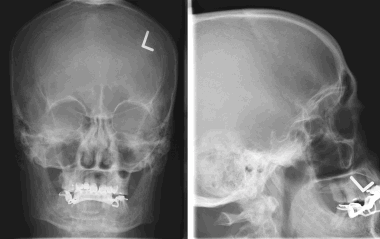

Псаммоматозная менингиома. КТ-исследование кальцифицированного объемного образования, обнаруженного на рентгеновском снимке. На томограмме, полученной на уровне верхней границы орбит, видна опухоль в области решетчатой пластинки (в области ольфакторной ямки).